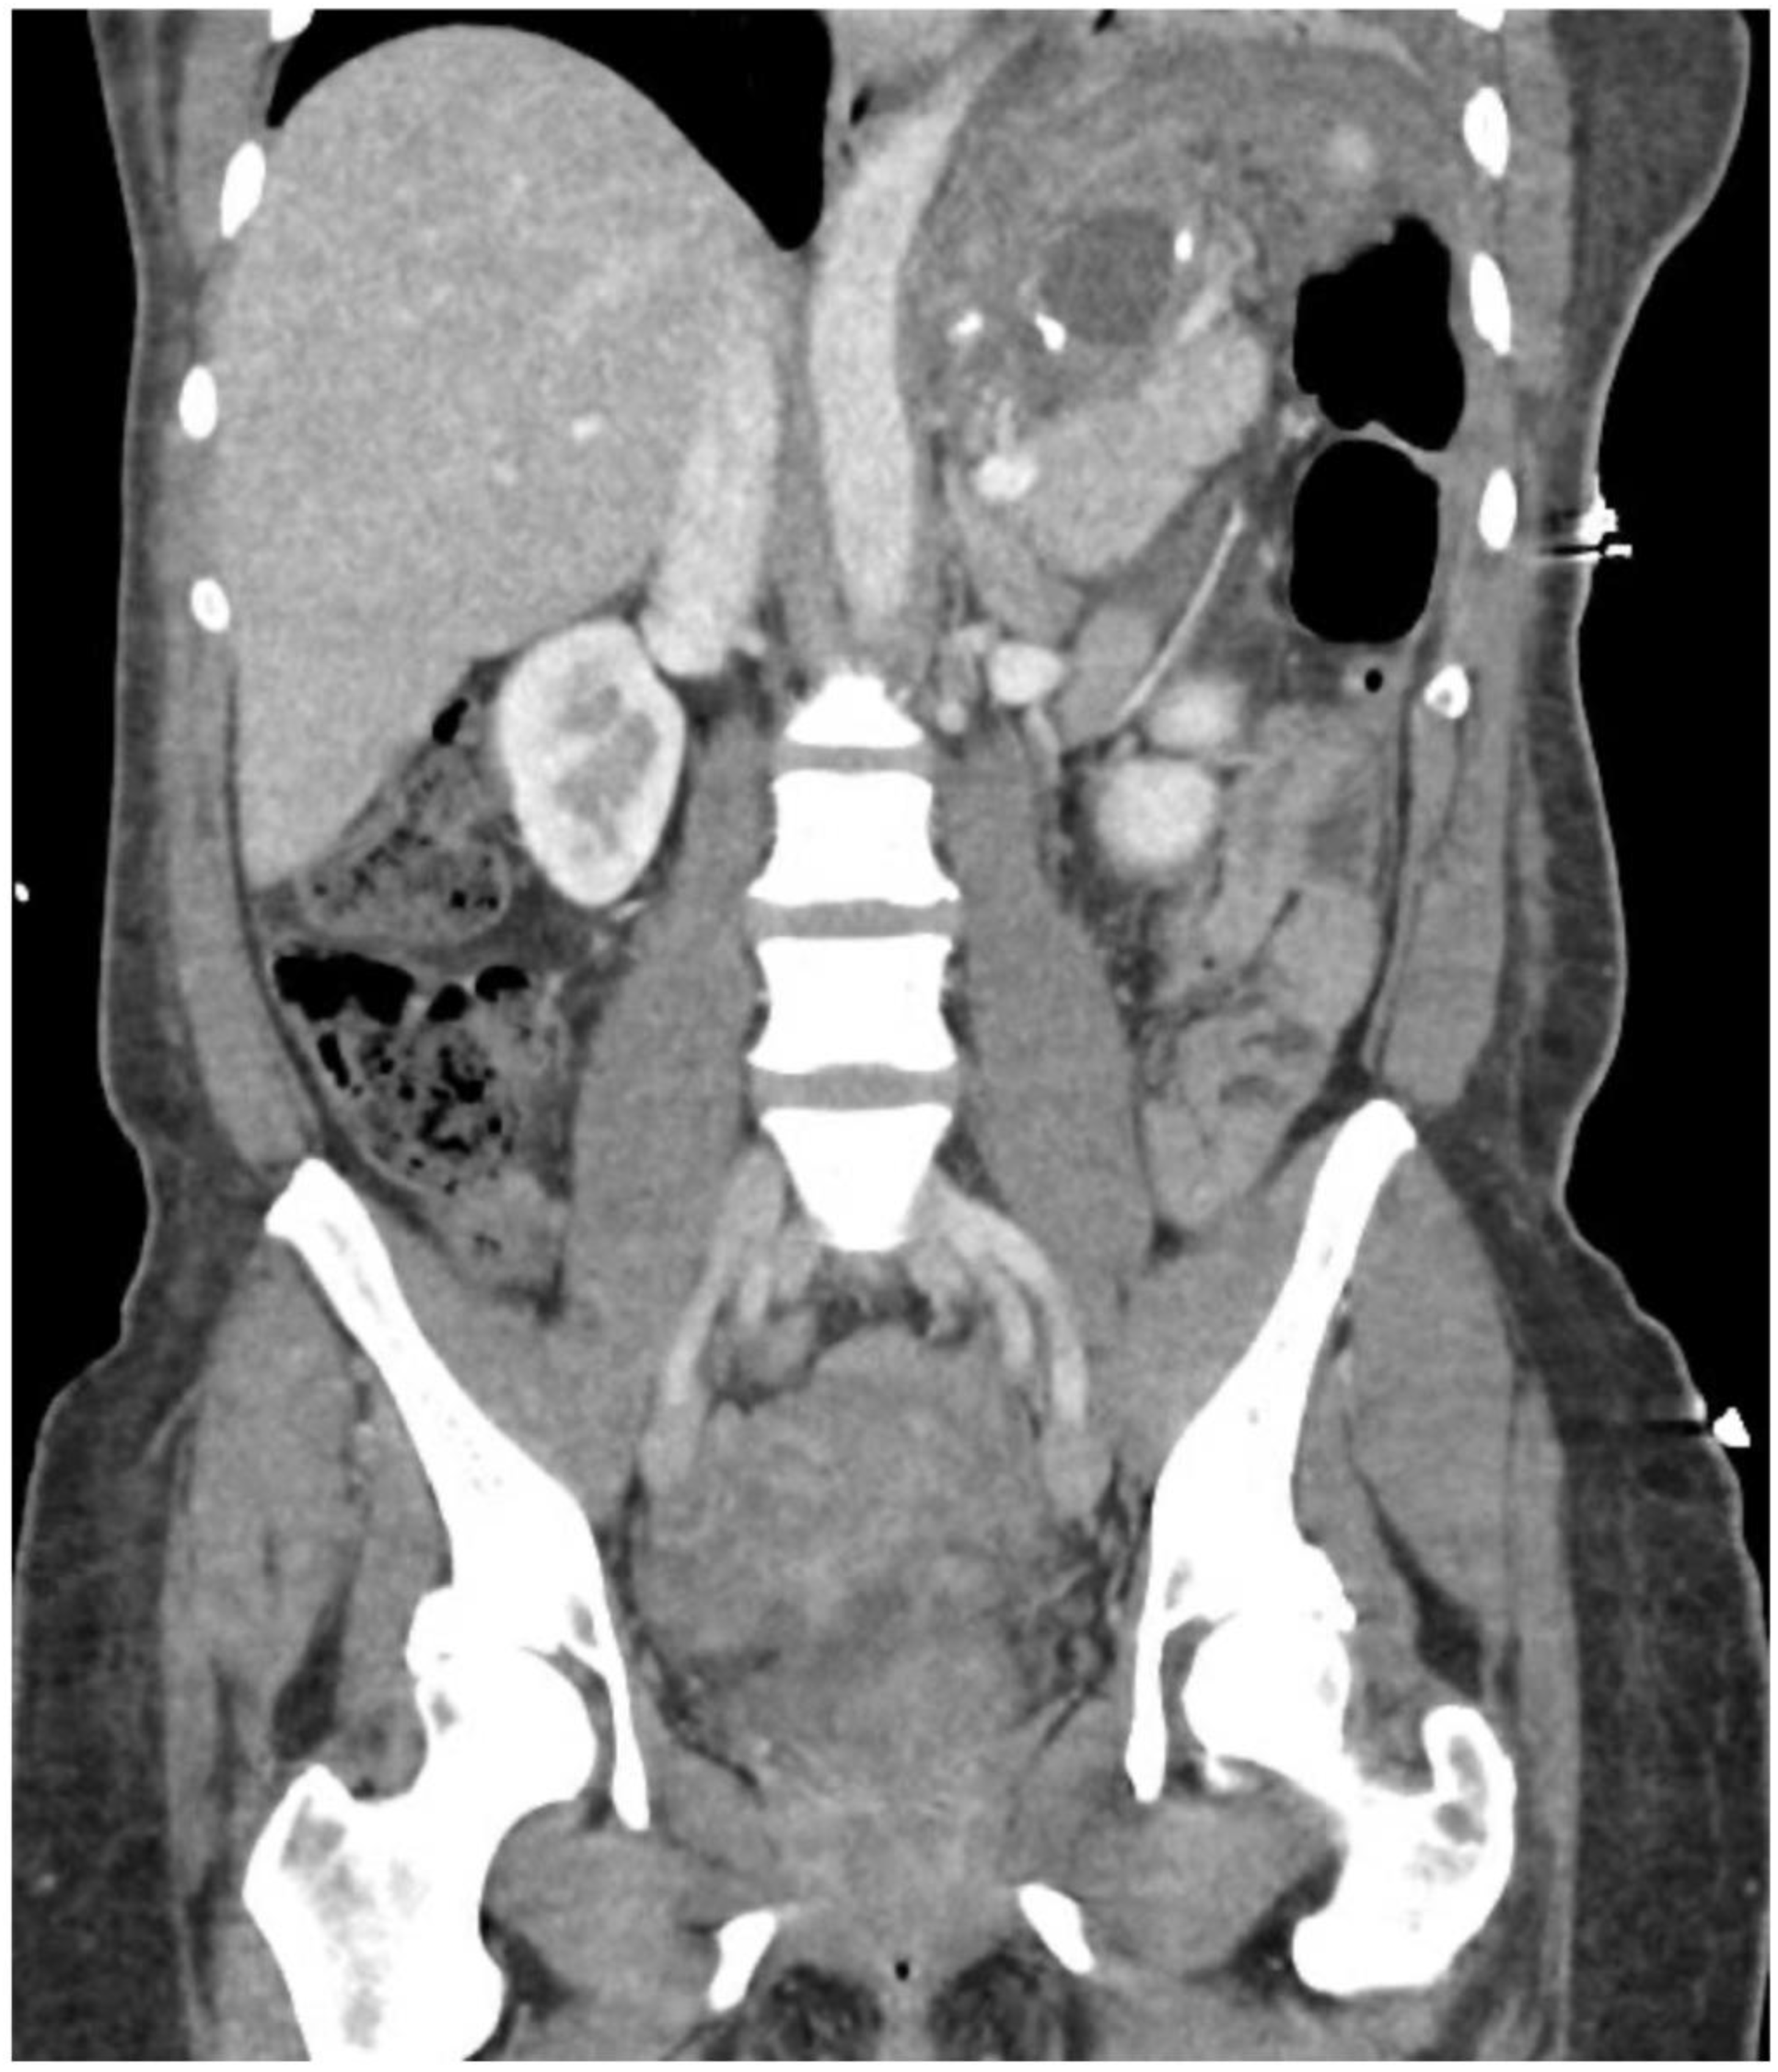

2. Detailed Case Description